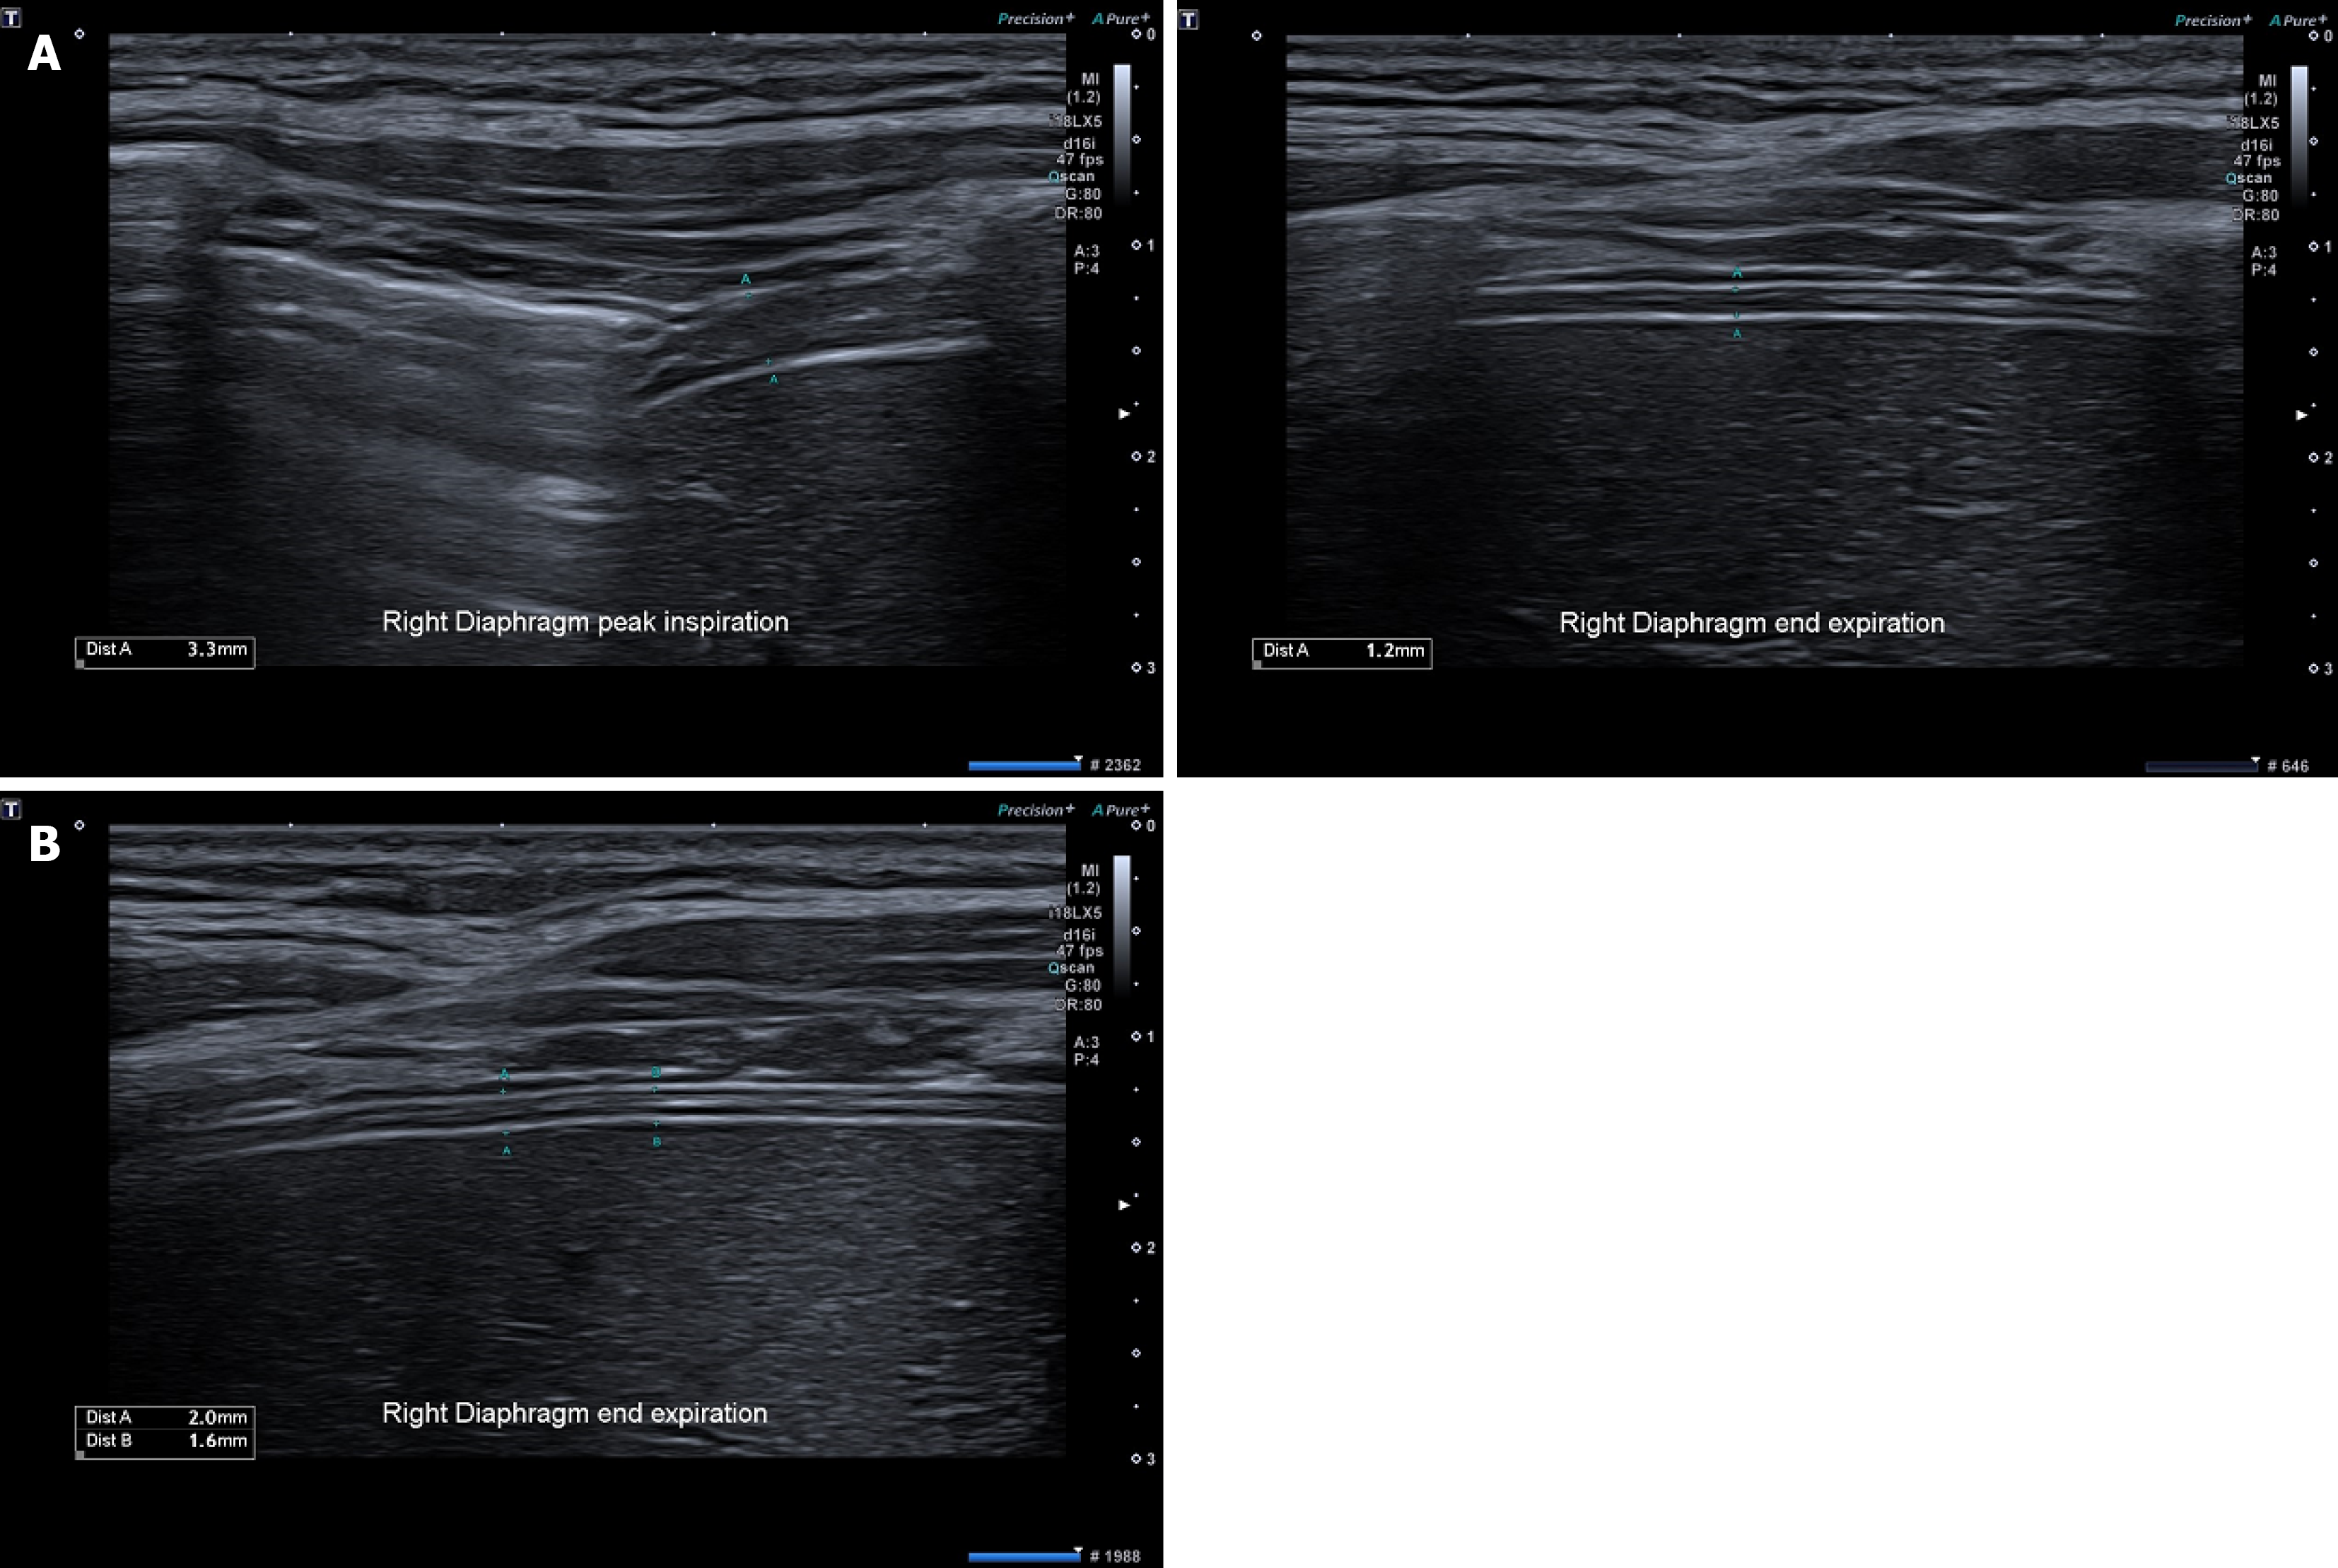

Figure 1 The measurements of diaphragmatic thickness.

A: Correct ways of measurements of diaphragm thickness at peak inspiration and end-expiration. Measurements A: Calipers placed within the two lines and not including the two lines into the total thickness; B: Examples of incorrect measurements of diaphragmatic thickness. Measurements A: Includes the two white lines into the measurement; measurements B: Includes the bottom white line into the measurement.